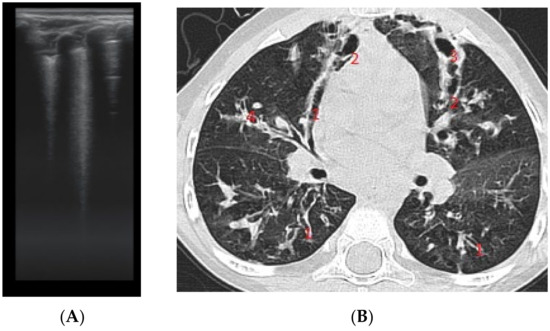

The assessment of LUS sensitivity and specificity in bronchiectasis detection varied with the form of bronchiectasis: for cylindrical bronchiectasis(Figure 8A,B), LUS Se = 77.7%, Sp = 9%, PPV = 80.7%, and NPV = 76.9%, while for saccular bronchiectasis (Figure 7), a moderate Se = 68.4%, with good Sp = 94.9%, PPV = 88.8%, and NPV = 94.7% were found.

As for varicose bronchiectasis (Figure 9 A,B), a very low Sp = 25% and NPV = 16.6% were calculated, with a satisfactory PPV = 88.8% and Se = 68.4%.

Figure 9. (A) LUS: coalescent B lines, loss of A lines. (B) CT image: (1) cylindrical bronchiectasis with moderate wall thickening; (2) varicose bronchiectasis; (3) saccular bronchiectasis with moderate wall thickening; and (4) several bronchiectasis with mucus plugging.